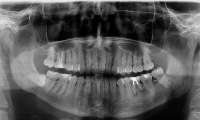

Стоматология Казааааах 26/01/24 Птн 11:27:33 1513634 1

Сап двач, вот что делать бедному студенту, который переживает за свои зубы? Конечно создать тред и спросить местных стоматологов. Стрелочкой я указал проблемный зуб. Сут такая: у меня там как бы трещина и получается так, что пропасть (хз как сказать) до десны доходит и там застревает еда, которую я вытаскиваю зубочисткой. Чем мне обернется отказ от лечения? Зуб не болит.

Не хочу тебя расстраивать, но у тебя там почти все зубы проблемные. И под пломбами с большой вероятностью вторичный кариес.

В смысле, что делать, пиздуй к стоматологу. У тебя все зубы не в порядке. Если запустишь, придётся протезировать. А сейчас полечишь кариес на 2-ке и 3-ке (Нерв сохранят, скорее всего) Пятёрке пизда, тут даже коронку не на что ставить. Плюс нужно удалить каличную восьмёрку и почистить зубной камень, который ты с рождения не чистил. И да, кстати, судя по всему 8-ка уже заразила кариесом 7-й зуб изнутри, ей тоже пизда.

Я не стоматолог, но тут прямо глазами даже нормису без кт видно, что лвойка, четверка, пятерка, шестера не очень.